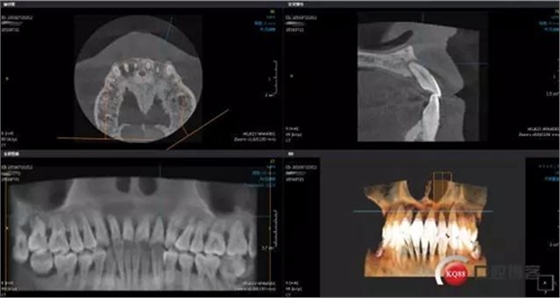

患者35歲,男,嚴(yán)重牙周病,身體體征健康,前牙區(qū)牙齒3度松動(dòng),求診修復(fù)

術(shù)前左上2 CBCT

術(shù)前右上2 CBCT